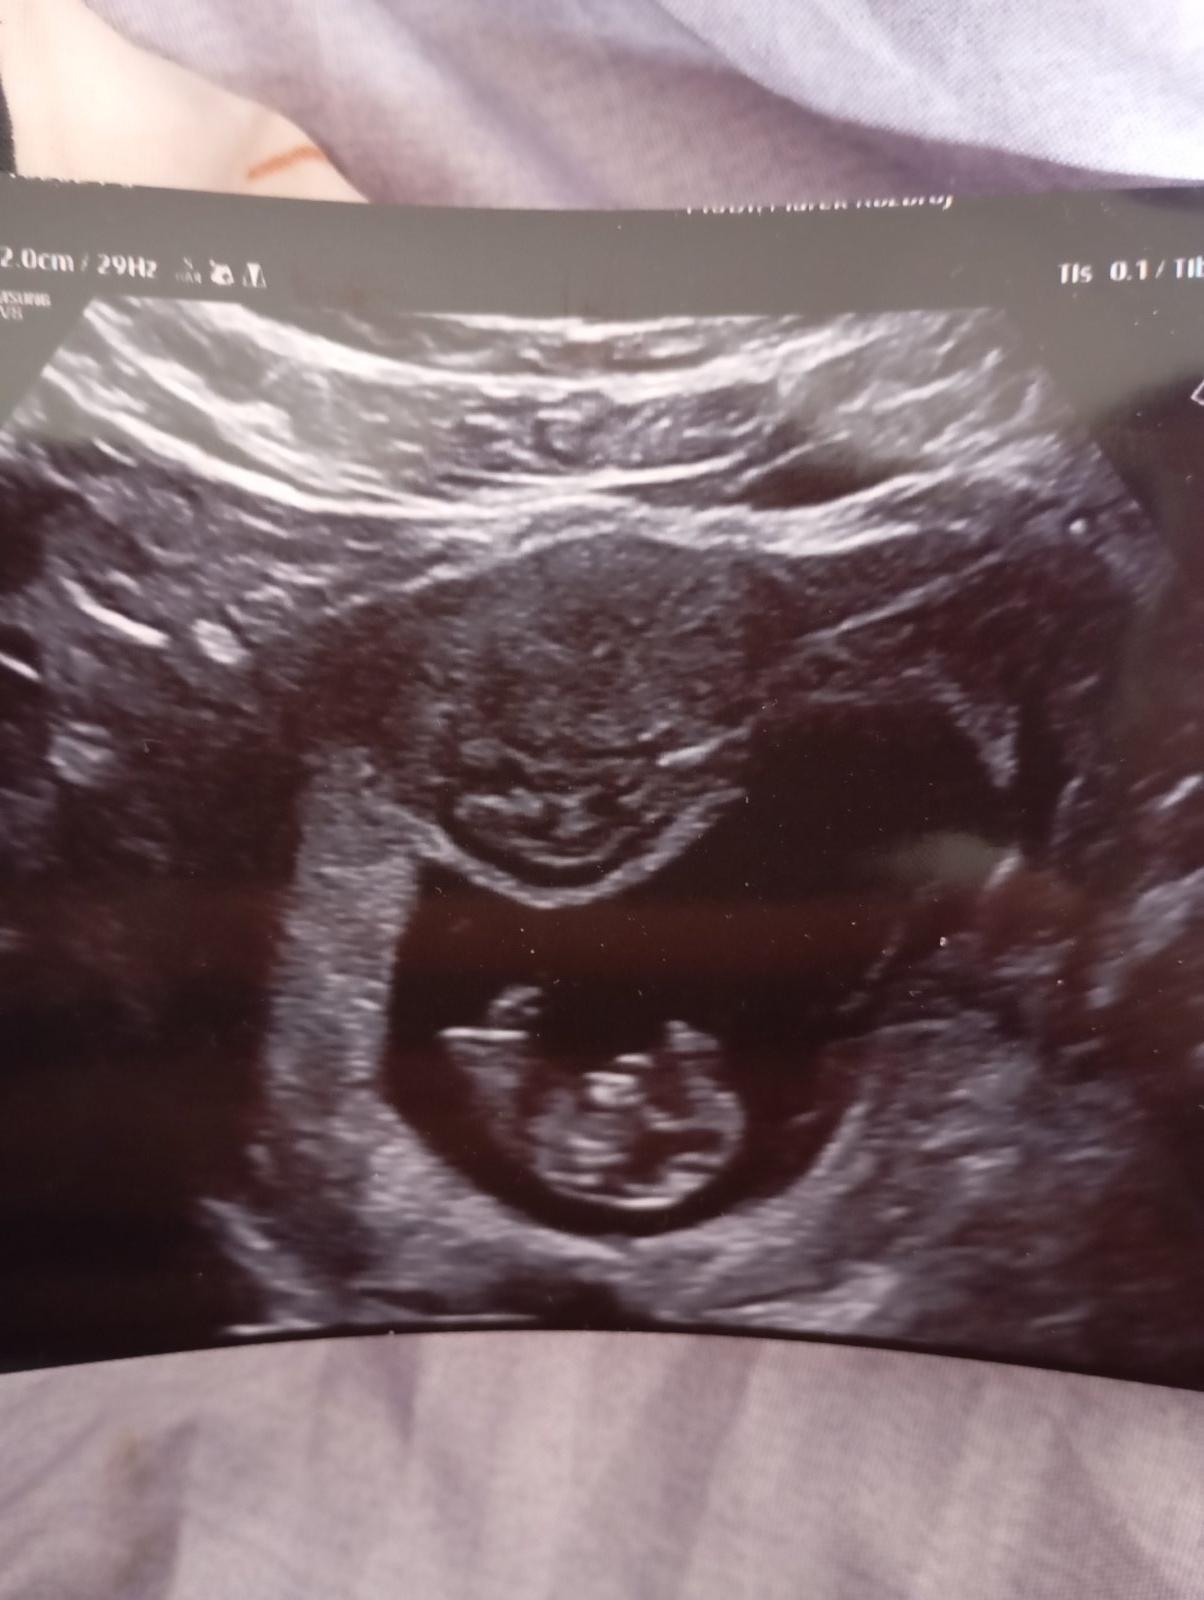

Je myom během těhotenství nebezpečný pro matku i dítě?

Já doufám v to že, bude vše v pořádku. Je to vymodlené miminko. 4 roky to nešlo a zázrakem se to teď stalo. A nebudu lhát dost se bojim i o sebe.

Celou dobu tam nic neviděli, az najednou teď nechápu. Minulý týden jsem taky byla na utz a nic